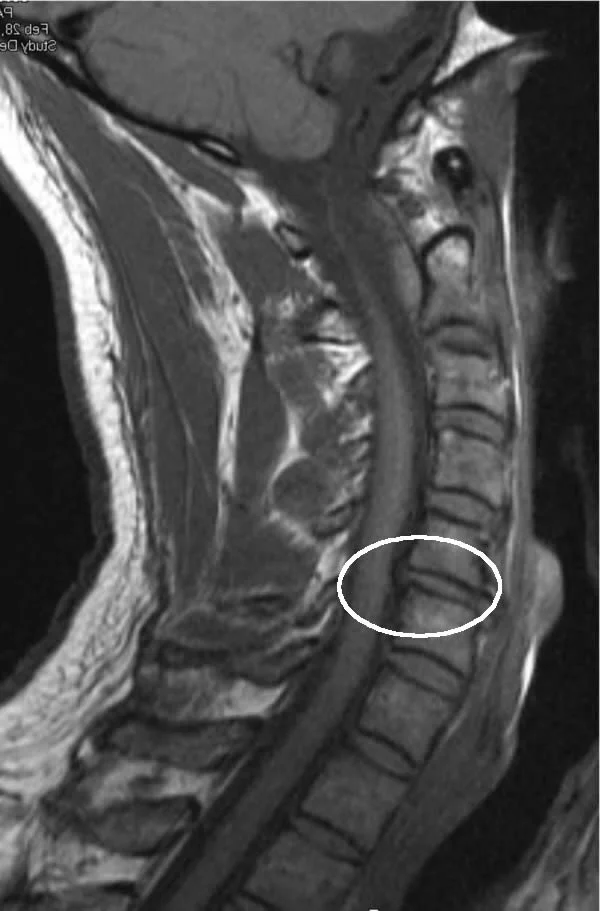

from csanjuan.org

Spine TinglingHow Artificial Disc Replacement Restores You In No Time

Spine TinglingHow Artificial Disc Replacement Restores You In No Time Neck Disc Tingling A herniated cervical disk is one of the most common causes of neck pain. Symptoms can vary depending on which disc has herniated and which nerve root has become pinched or inflamed. Cervical herniated disc pain and related signs are typically felt in one arm or the other. These types of symptoms can interfere with daily activities,. An irritated nerve. Neck Disc Tingling.